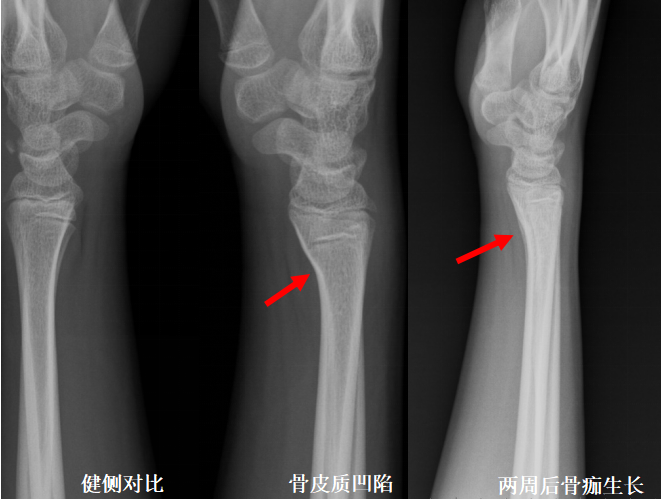

X线检查是骨折首选的影像学检查手段,可以达到快速初步判断的目的

X线检查具有成像速度快、费用低、辐射少的优点,对于有移位的骨折、骨质破坏、关节骨病、不透光异物存留等疾病有很好的诊断价值,因此X线检查成为骨折的首选检查方法。

明显的骨折通过X线片就可以明确诊断,达到辅助临床医生诊断及治疗的目的,复位后只需要遵医嘱并定期复查即可。

然而X线检查并非十全十美,它对肌肉软组织的分辨率低、仅显示照射范围内所有器官的重叠影像,对重叠部位、复杂部位、细微骨折等容易出现漏诊、误诊的情况。